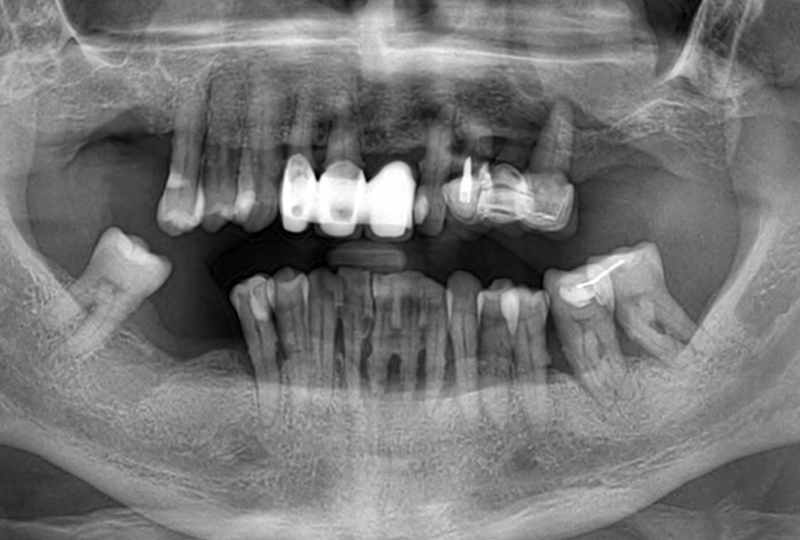

Il paziente di 57 anni, in buono stato di salute generale, si presentava con una vecchia riabilitazione con protesi fissa superiore, con i pilastri dentali a supporto delle protesi e i denti dell’arcata inferiore con un’elevata compromissione parodontale (Figure 1,2).

La proposta protesica fu una riabilitazione fissa supportata da impianti sia per l’arcata superiore che per quella inferiore, attraverso tecnica All-on 4. Prima della fase chirurgica, in un unico appuntamento, venivano acquisite le foto extra-orali in posizione di riposo, con un sorriso appena accennato, il massimo sorriso possibile, la CBCT delle arcate (ProMax 3D® Planmeca), le scansioni orali (TRIOS® 3, 3Shape) e le scansioni facciali (POP-2®, Revopoint) con un repere di posizionamento, in posizione di riposo e massimo sorriso. Con queste informazioni era possibile procedere, attraverso due sessioni di chirurgia eseguite secondo la tecnica All-on-4, al posizionamento di due protesi fisse a carico immediato in PMMA (Ceramill A-temp®, Amann Girrbach) (Figure 3,4).